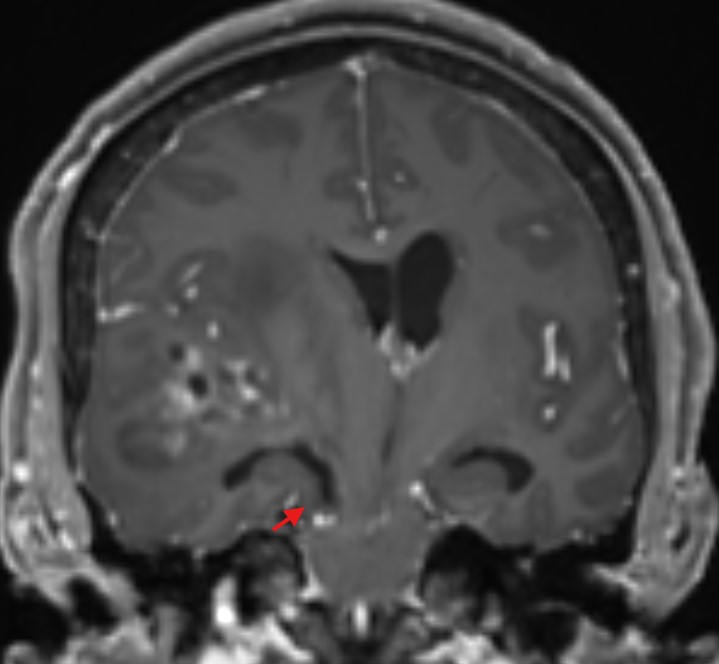

Unkale Herniation im MRi

Darstellung eines axialen und coronaren T2 MRI Bild mit einer unkalen Herniation (roter Pfeil).